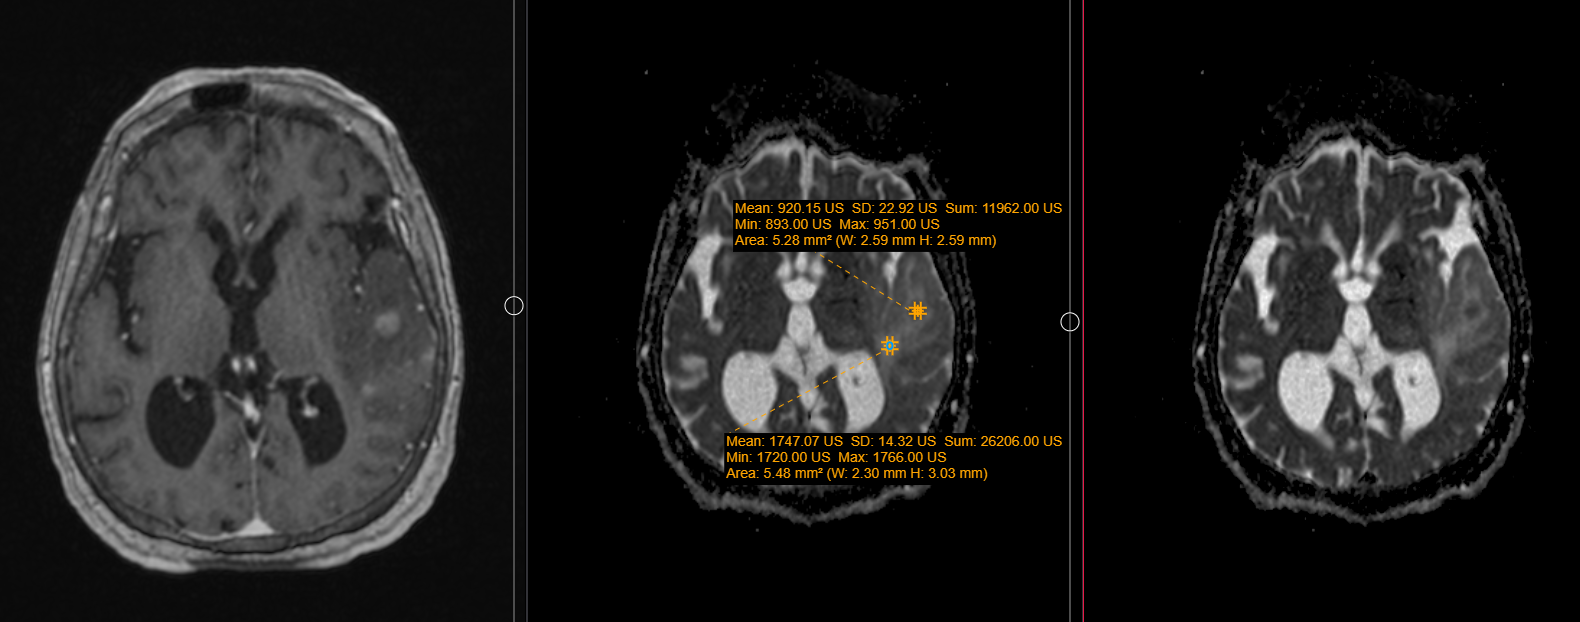

This is particularly valuable in brain tumors. While conventional sequences may show lesion location and edema, diffusion imaging reveals changes within the tissue itself.

Apparent Diffusion Coefficient (ADC) mapping serves as a fundamental quantitative tool in neuro-oncology (Figure 4). In this representative case of high-grade glioma, the solid component of the lesion demonstrates restricted diffusion with a diminished ADC value of 0.92 × 10⁻³ mm²/s, reflecting increased cellular density. Glioblastomas often exhibit such low mean diffusivity values due to restricted water motion from high cellular density. Conversely, the peritumoral vasogenic edema exhibits an elevated ADC value of 1.74 × 10⁻³ mm²/s, consistent with increased extracellular water mobility.

Diffusion kurtosis imaging may additionally show high kurtosis values, indicating the complex microstructural architecture typical of aggressive tumors.

These metrics help characterize tumors beyond what conventional imaging can reveal.

Figure 2: Diffusion MRI in a representative case of high-grade glioma. (A) Axial contrast-enhanced T1-weighted image showing the intra-axial mass lesion with surrounding vasogenic edema. (B) Corresponding apparent diffusion coefficient (ADC) map. Quantitative region-of-interest (ROI) analysis demonstrates restricted diffusion in the solid tumor component (yellow ROI: mean ADC = 0.92 × 10⁻³ mm²/s) and elevated diffusivity in the peritumoral vasogenic edema (blue ROI: mean ADC = 1.74 × 10⁻³ mm²/s). (C) Axial diffusion-weighted imaging (DWI, b = 1000 s/mm²) trace image. Courtesy of Christos Tsiotsios (Author).